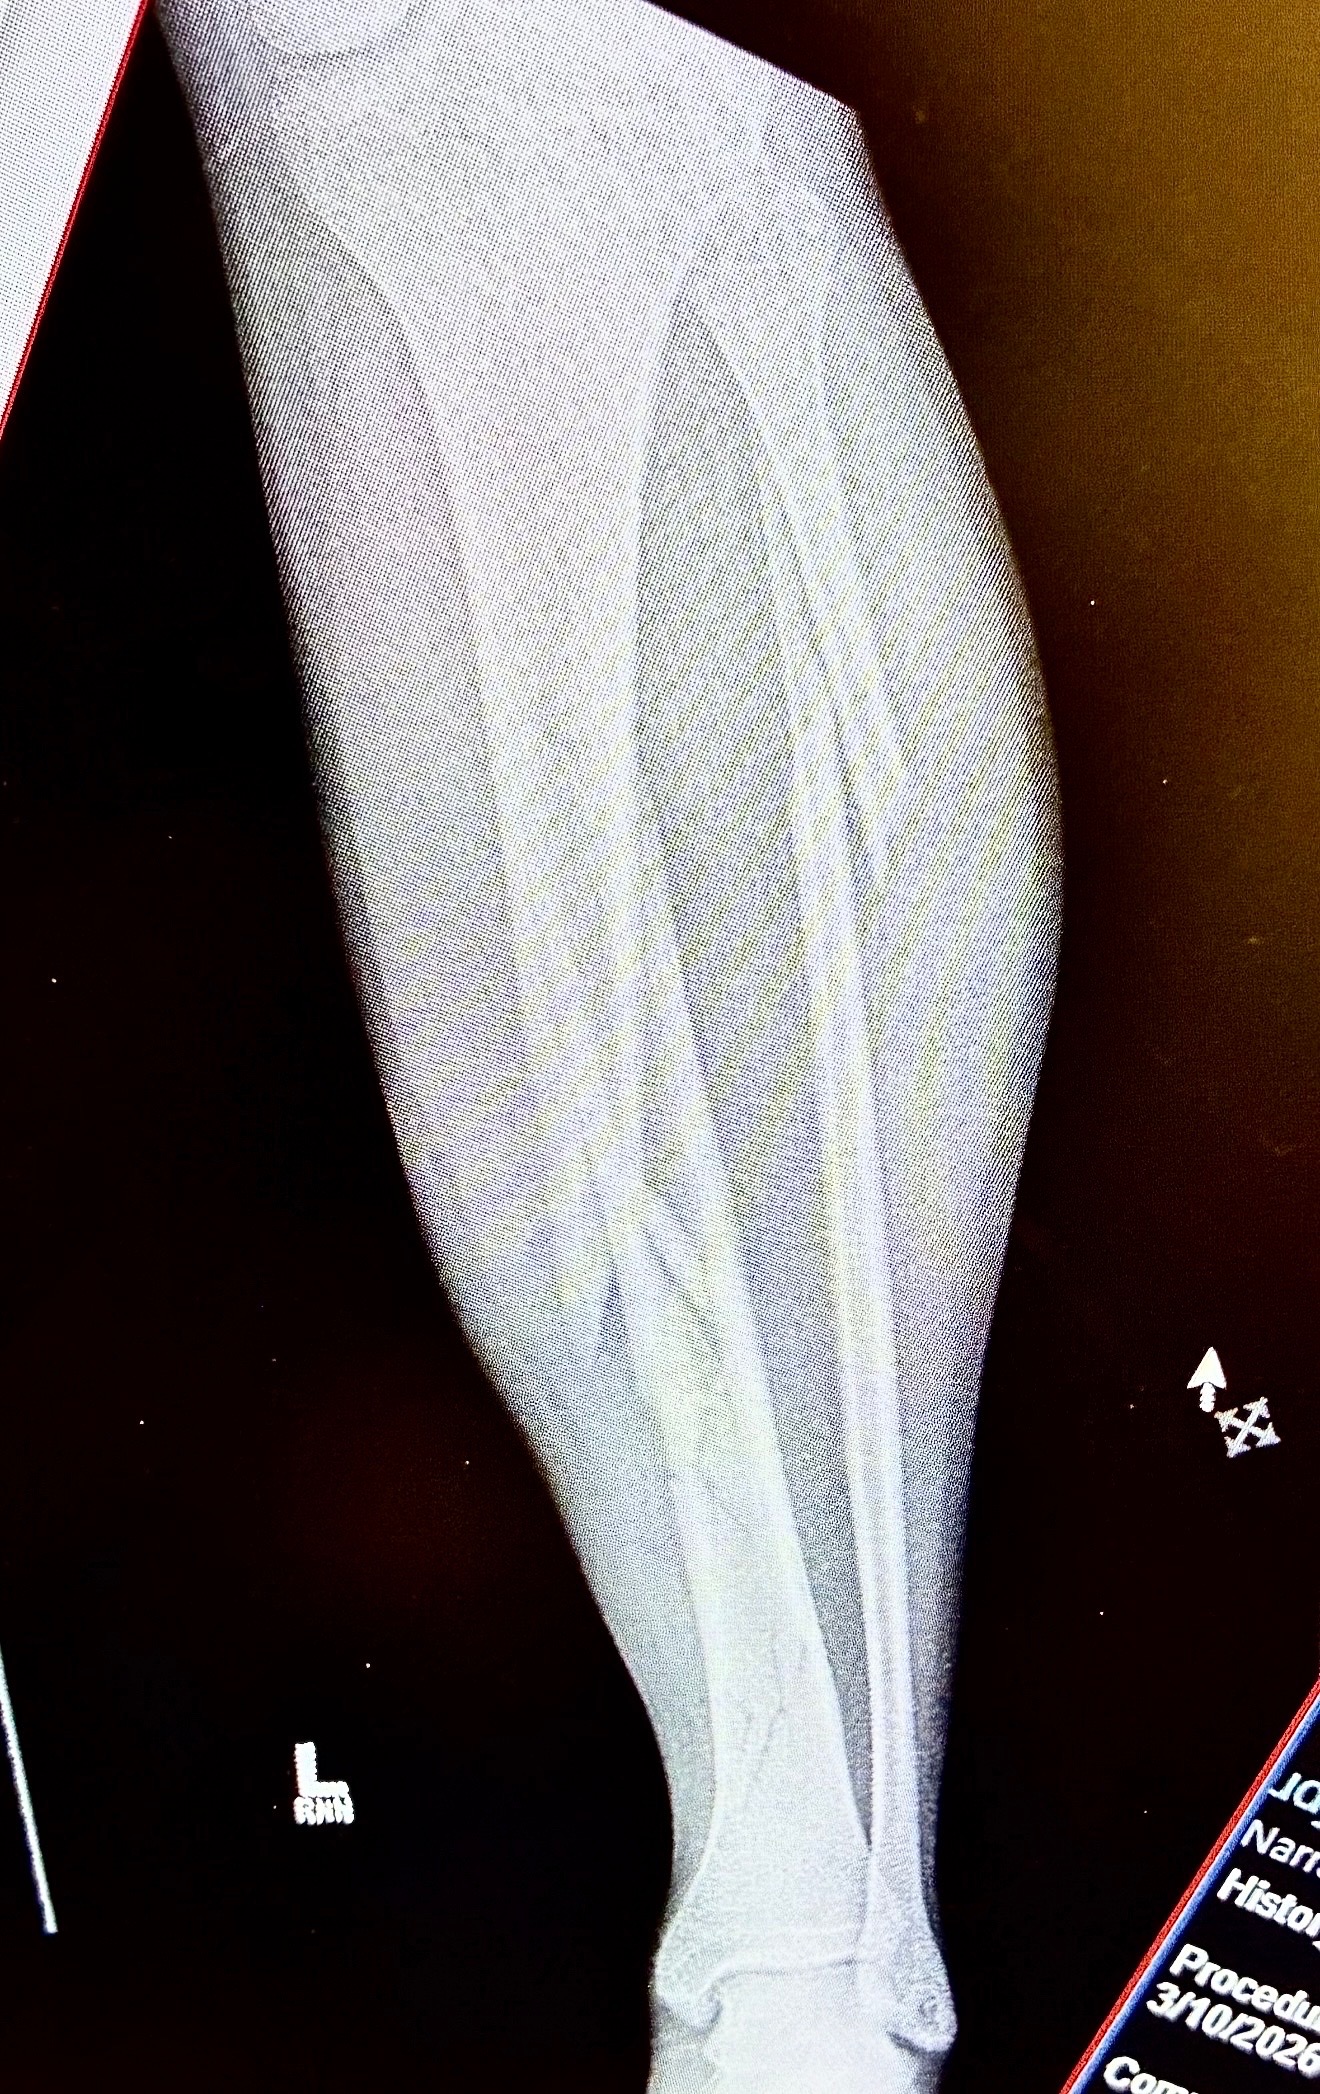

Our son, Cayen Ridge, was recently involved in a serious motorcycle accident after a driver ran a red light and struck him. In an instant, his life was turned upside down literally . After doing 3 front flips through the air somehow his left leg managed to take the brunt of the crash.Iit is truly by God’s grace, Cayen survived, but he is now facing a long road to recovery. While he does have insurance, the reality is that the copays and out-of-pocket medical expenses are overwhelming, with his leg being shattered he has to see the surgeon every two weeks. On top of that, he is currently unable to work, leaving him without a way to keep up with his everyday bills while he heals. He can apply for disability, but we were told by the California police department it could take up to 3months to get his police report back.